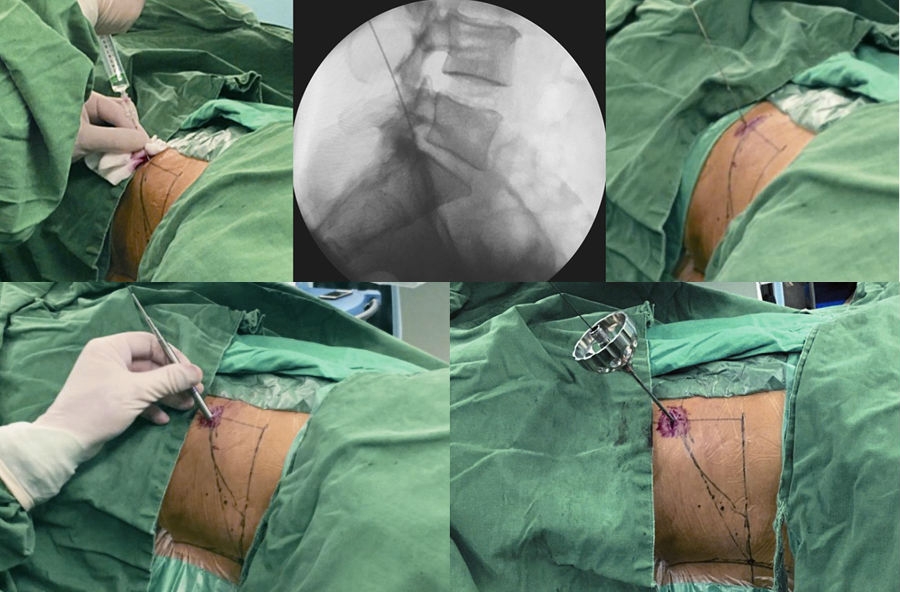

患者取侧卧位,患侧在上,健侧腰部垫高,以健侧髂骨刚离开床面为宜。(图3)

2. 手术入路

取后外侧入路,穿刺点L3~4为后正中线旁开 8~10cm,L4~5为 10~12cm,L5~S1为12~14cm,肥胖者各节段较普通患者多旁开1~2cm。(图 4)

使用1%利多卡因40ml进行逐层局部浸润麻醉,包括皮下组织、深筋膜和关节突关节。(图 5)

4. 穿刺

以L5~S1为例,根据髂嵴的高低,针尾向头侧倾斜约 40°~60°,外展角约 30°~50°,定位针在正位X线透视下刚好位于后背正中的棘突连线上,侧位X线透视下则紧贴上关节突腹侧,下缘位于下位椎体的后上缘。(图6)

5. 穿刺点

做大约1cm皮肤切口,用导丝置换穿刺针,沿导丝用扩张器逐级扩大软组织。(图7、图8)

图3 定位板前后位X线片标定靶点和穿刺方向

A. 术前定位板标记体表位置;B.定位板X线射片投影图

图4 标记穿刺线

A. L5-S1椎间盘平面;B.棘突中线连线;C.穿刺假想体表投影

图5-图9 A:使用利多卡因进行局部分层麻醉(皮肤、皮下组织、筋膜、关节突周围);B:穿刺针X线片侧位投影图;C:穿刺到位后交换导丝;D:导丝引导下通过导杆、三级套管扩张肌肉及软组织;E:导丝引导下交换Tom针,定位上关节突